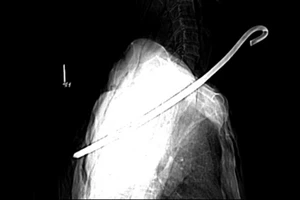

Các bác sĩ phẫu thuật cấp cứu lấy chiếc kéo đâm xuyên cổ bệnh nhân

keo-dam-xuyen-co-1.jpg